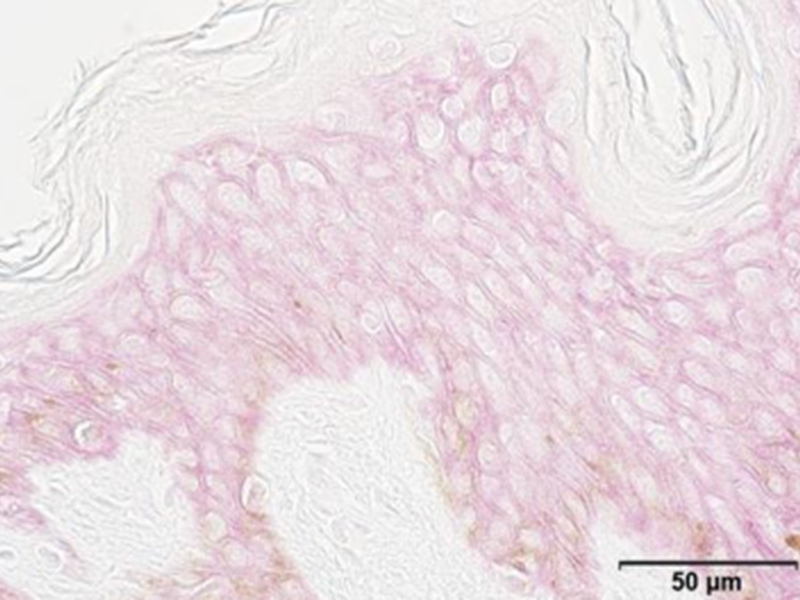

Samphire Native Plant Cells were tested on reconstructed skin (human full-thickness model, systemic application) and demonstrated a significant decrease of -18% of ozone-induced increase of oxidative markers 8-isoprostane [2].

[2] In-vitro test on reconstructed skin exposed 2 times for 18 hours to O3, 3 days of systemic application of native Crithmum maritimum cells